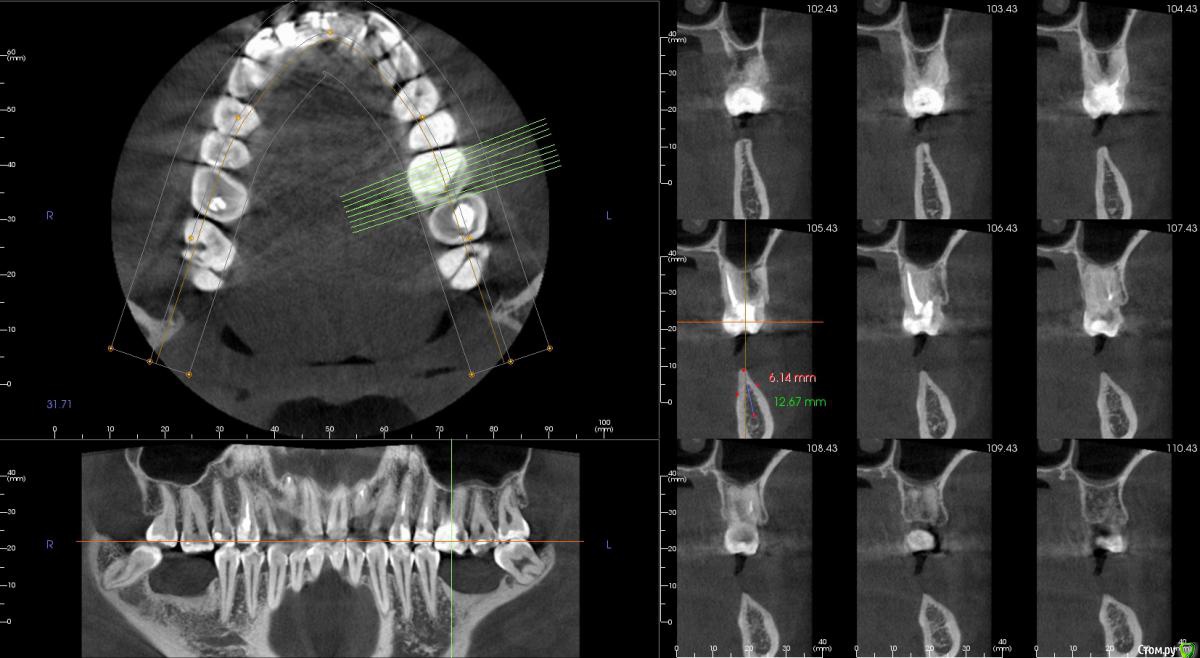

Господа как лучше тут поступить? поменьше бы рисков)

" всеводинэтап"крыша гаража" и латерализация отменяются)))

вижу вариант только с сеткой.

Из того что разобрал по срезам мне кажется можно медиально расщепить и притопить, дистально 4х6 поставить (астра, штрауманн...). Посмотрите, помещаются ли такие импланты. Травма меньше, быстрее и меньше рисков.